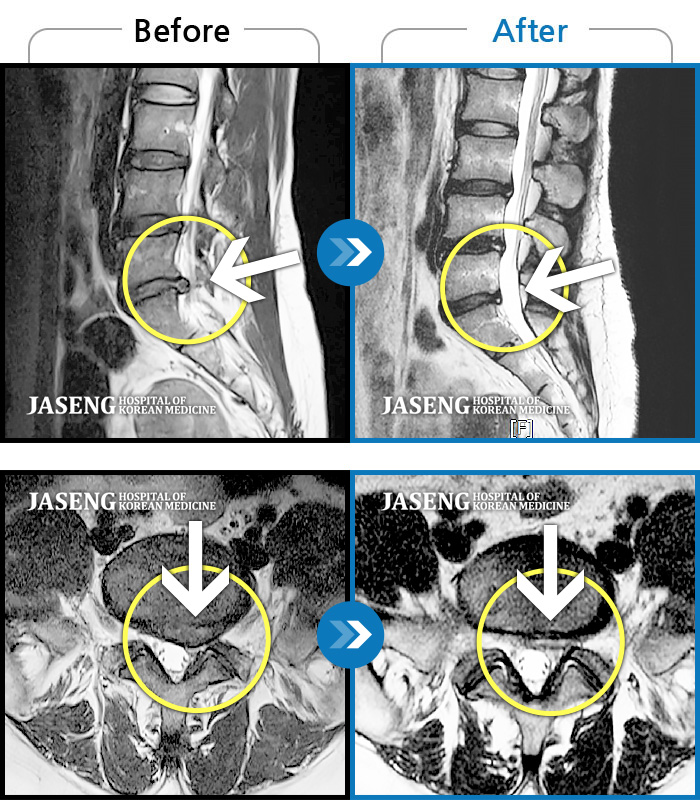

MRI 치료사례

허리 통증과 왼쪽 다리 저림이 너무 심해서 걷기도 잠자기도 힘들었어요